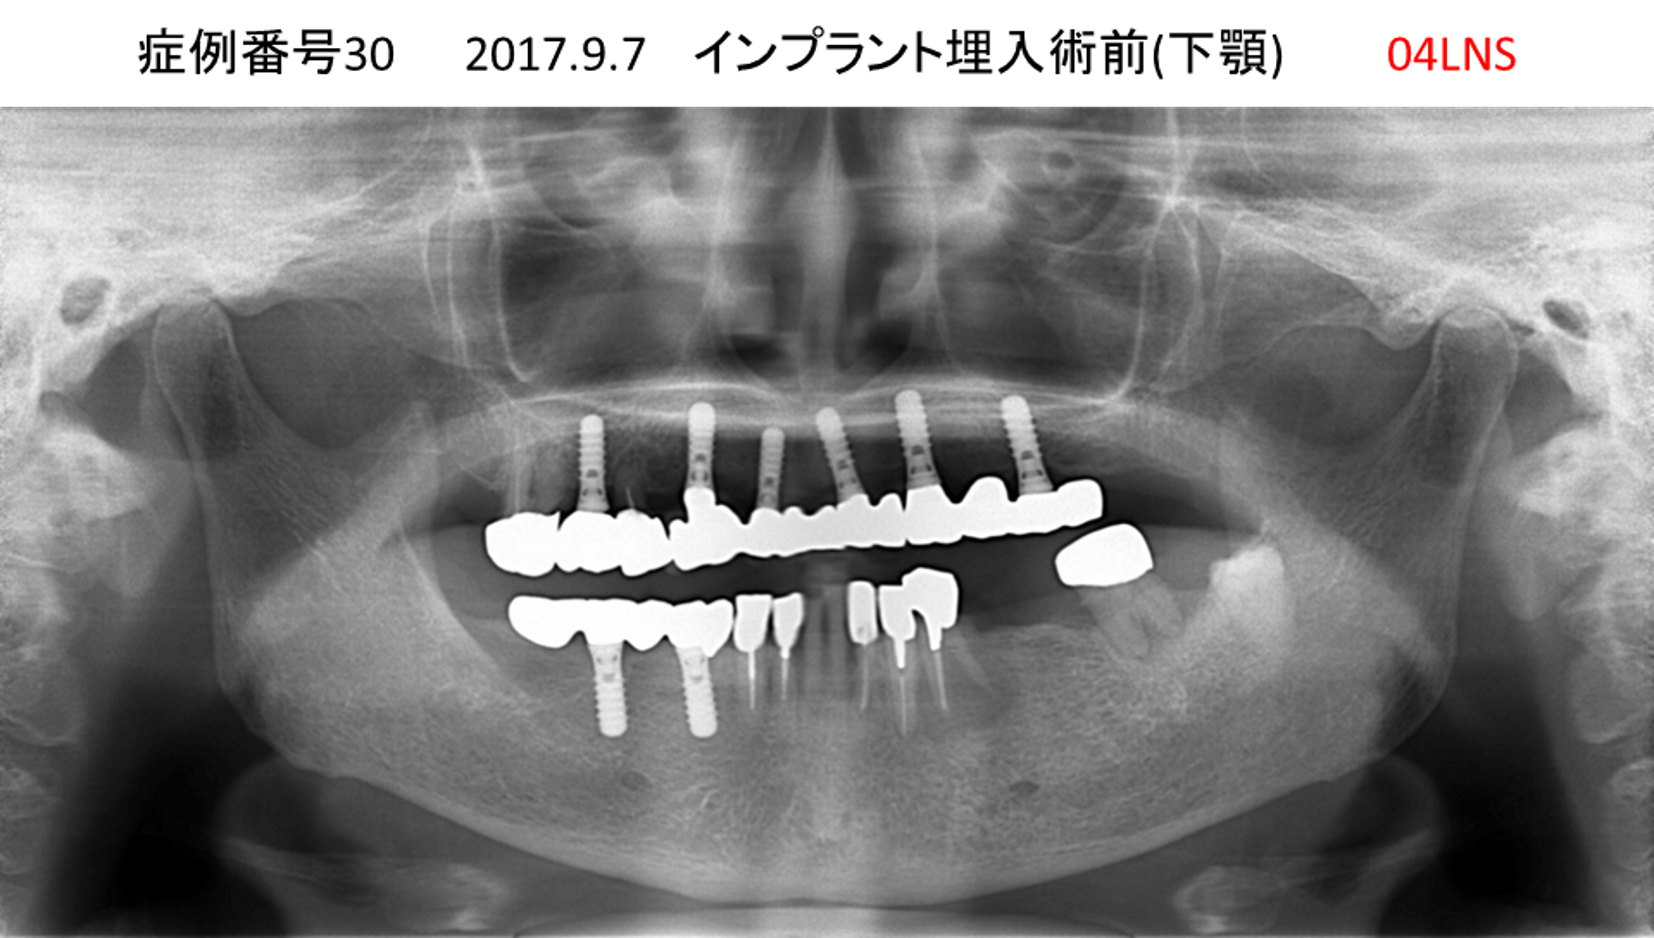

全く噛めない患者様のインプラント症例

| 治療名称 |

インプラントAGC |

| 治療費用 |

860万円+税 |

| 治療期間 |

12か月 |

| 患者さんの症状(主訴) |

全く噛めない、ごはんが後もに食べられるようになりたい、人前で口元を隠したくない |

| 治療内容 |

サイナスリフト、GBR、インプラント、AGC |

| 治療結果 |

しっかり噛めて踏ん張ることができる。食べ物をを選ばなくて済む、何でも食べられる、体重が増えた。見栄えがきれいすぎて自分じゃないみたい |

| 治療の注意点(リスク/副作用) |

インプラントが壊れたら再治療が必要 |